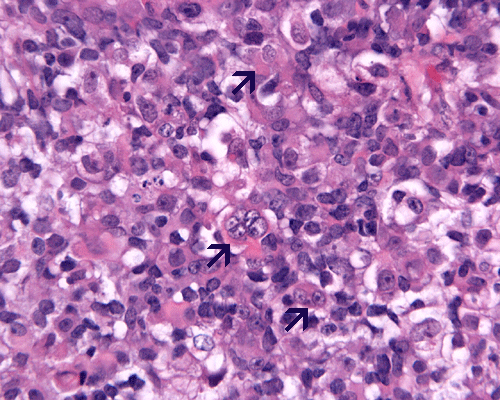

Pathology

Rhabdoid cells are medium sized to large, oval to round cells. In the most classic example, the rhabdoid cell contains an eosinophilic, hyaline-like cytoplasmic globule resembling an inclusion body and occupies a large portion of the cytoplasm. This hyaline globule displays the nucleus to an eccentric location. The less classic examples contain a substantial amount of eosinophilic, often hyaline-like cytoplasm and eccentrically located nuclei. Although the morphologic features are suggestive of a rhabdomyosarcoma, cytoplasmic striations typical for rhabdomyoblastic differentiation should not be present. Marked pleomorphism is seen in most cases and nucleoli are usually prominent. Multinucleated giant cells are common. Mitotic figures and atypical mitosis are common. The degree of necrosis is variable but may not be extensive.

Only about 13% of AT/RTs are composed exclusively of rhabdoid cells. Non-rhabdoid components are seen in the rest. About two third to three quarter of AT/RTs are associated with medulloblastoma or primitive neuroectodermal tumor (PNET) like components. Neoplastic epithelial components may occur as adenocarcinoma-like components, squamous cell with keratinization, or just simply epithelial cells arranged in nests. Neoplastic mesenchymal components can also be seen. The amount of rhabdoid cells can vary greatly from uncommon to substantial. AT/RT with substantial medulloblastoma/PNET like component may be mistaken as medulloblastoma or PNET [Burger PC et al., 1996]. Under the electron microscopy, rhabdoid cells contain bundles of tightly packed intermediate filaments arranged in whorls.